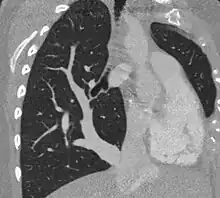

| Scimitar syndrome chest CT | |

Diagnosis

The diagnosis is made by transthoracic or transesophageal echocardiography and selective pulmonary angiography.[5] More recently by CT angiography or MR Angiography.

Pulmonary angiography demonstrates anomalous arterial supply to right lower lobe.[5]